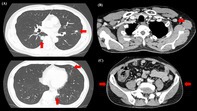

在全球范围内,梅毒病例一直在增加,并报告了肺部病变。然而,无症状的神经梅毒尚未被记录。这种情况往往不为人所知,其症状与其他传染性和非传染性肺部疾病相似。在被定义为梅毒的第二种形式的梅毒肺炎中,肌肉注射青霉素(2400万单位)仍然是治疗的金标准,预后良好。本文首次报道一例无症状性神经梅毒伴多发肺结节和臀部脂肪营养不良。如果快速血浆反应素(RPR)抗体滴度高且随访时RPR检测困难,可考虑脑脊液(CSF)检查以进一步评估无症状神经梅毒。本例RPR高表达(154 ruu),且由于患者工作性质(长途运输),短期随访困难。因此,采用脑脊液进行早期诊断和治疗。

Globally, syphilis cases have been increasing and pulmonary lesions have been reported. However, asymptomatic neurosyphilis has not been documented. This condition is often unrecognised and presents with symptoms similar to those of other infectious and non-infectious lung diseases. In syphilitic pneumonia, defined as a secondary form of syphilis, intramuscular injection of benzylpenicillin (24 million units) remains the gold standard for treatment, with a favourable prognosis. This report presents for the first time a case of asymptomatic neurosyphilis with multiple pulmonary nodules and buttock lipodystrophy. If rapid plasma reagin (RPR) antibody titres are high and RPR testing is difficult during follow-up, cerebrospinal fluid (CSF) examination may be considered for further evaluation of asymptomatic neurosyphilis. This case showed a high expression of RPR (154 R.U.) and given the nature of the patient's work (long-distance transportation), short-term follow-up was difficult. Therefore, CSF was performed to enable early diagnosis and treatment.